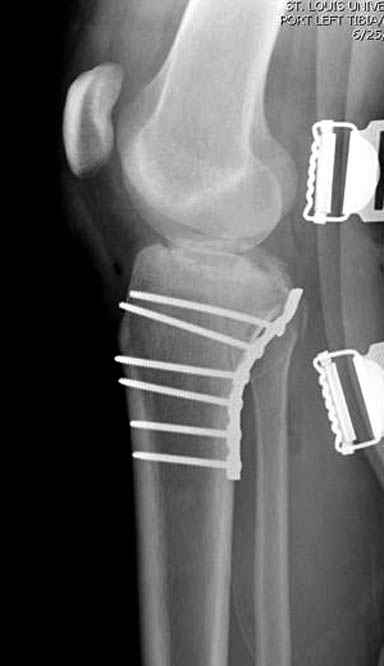

Трудно поверить, что разрекламированная Ортопедическая школа Восточной Украины позволяет такие странные снимки? На прямом снимке сохранен общий контур плато, но не известна судьба импрессии суставной поверхности. На полубоковой?, оставлен без репозиции задне-медиальный отдел, и навряд ли после такой фиксации можно удовлетвориться результатом.

Такая ситуация характерна для многих, когда принимается ошибочное решение, т.е пытаются фиксировать одним имплантом переломы двух мыщелков. Латеральная пластина приемлема только для тех случаев, когда сохраняется интактным медиальный диафизарный кортекс и отсутствует фрагментация на верхушке медиального перелома.

Здесь как раз тот случай, когда результат зависит не только от мастерства хирурга, но и от наличия современных методов исследования. Например, КТ которая поможет рассчитать направления шурупов и установку импланта. Кроме этого, поможет определиться с доступом.

Представленные снимки не информативны, нужны отдельные качественные снимки коленного сустава и голени без ротации.